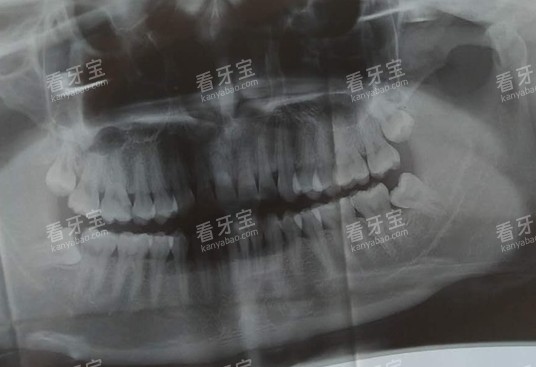

头一步是检查和麻醉。医生会先通过肉眼观察和X光片,确认牙齿的损坏程度、根管数量和位置,然后在牙齿周围打局部麻药,等麻药起效后再开始治疗,这样能比较大程度减轻疼痛感。麻药起效后,医生会用专门的工具把牙齿上的蛀坏部分清理干净,打开牙髓腔,露出里面感染的神经和血管。